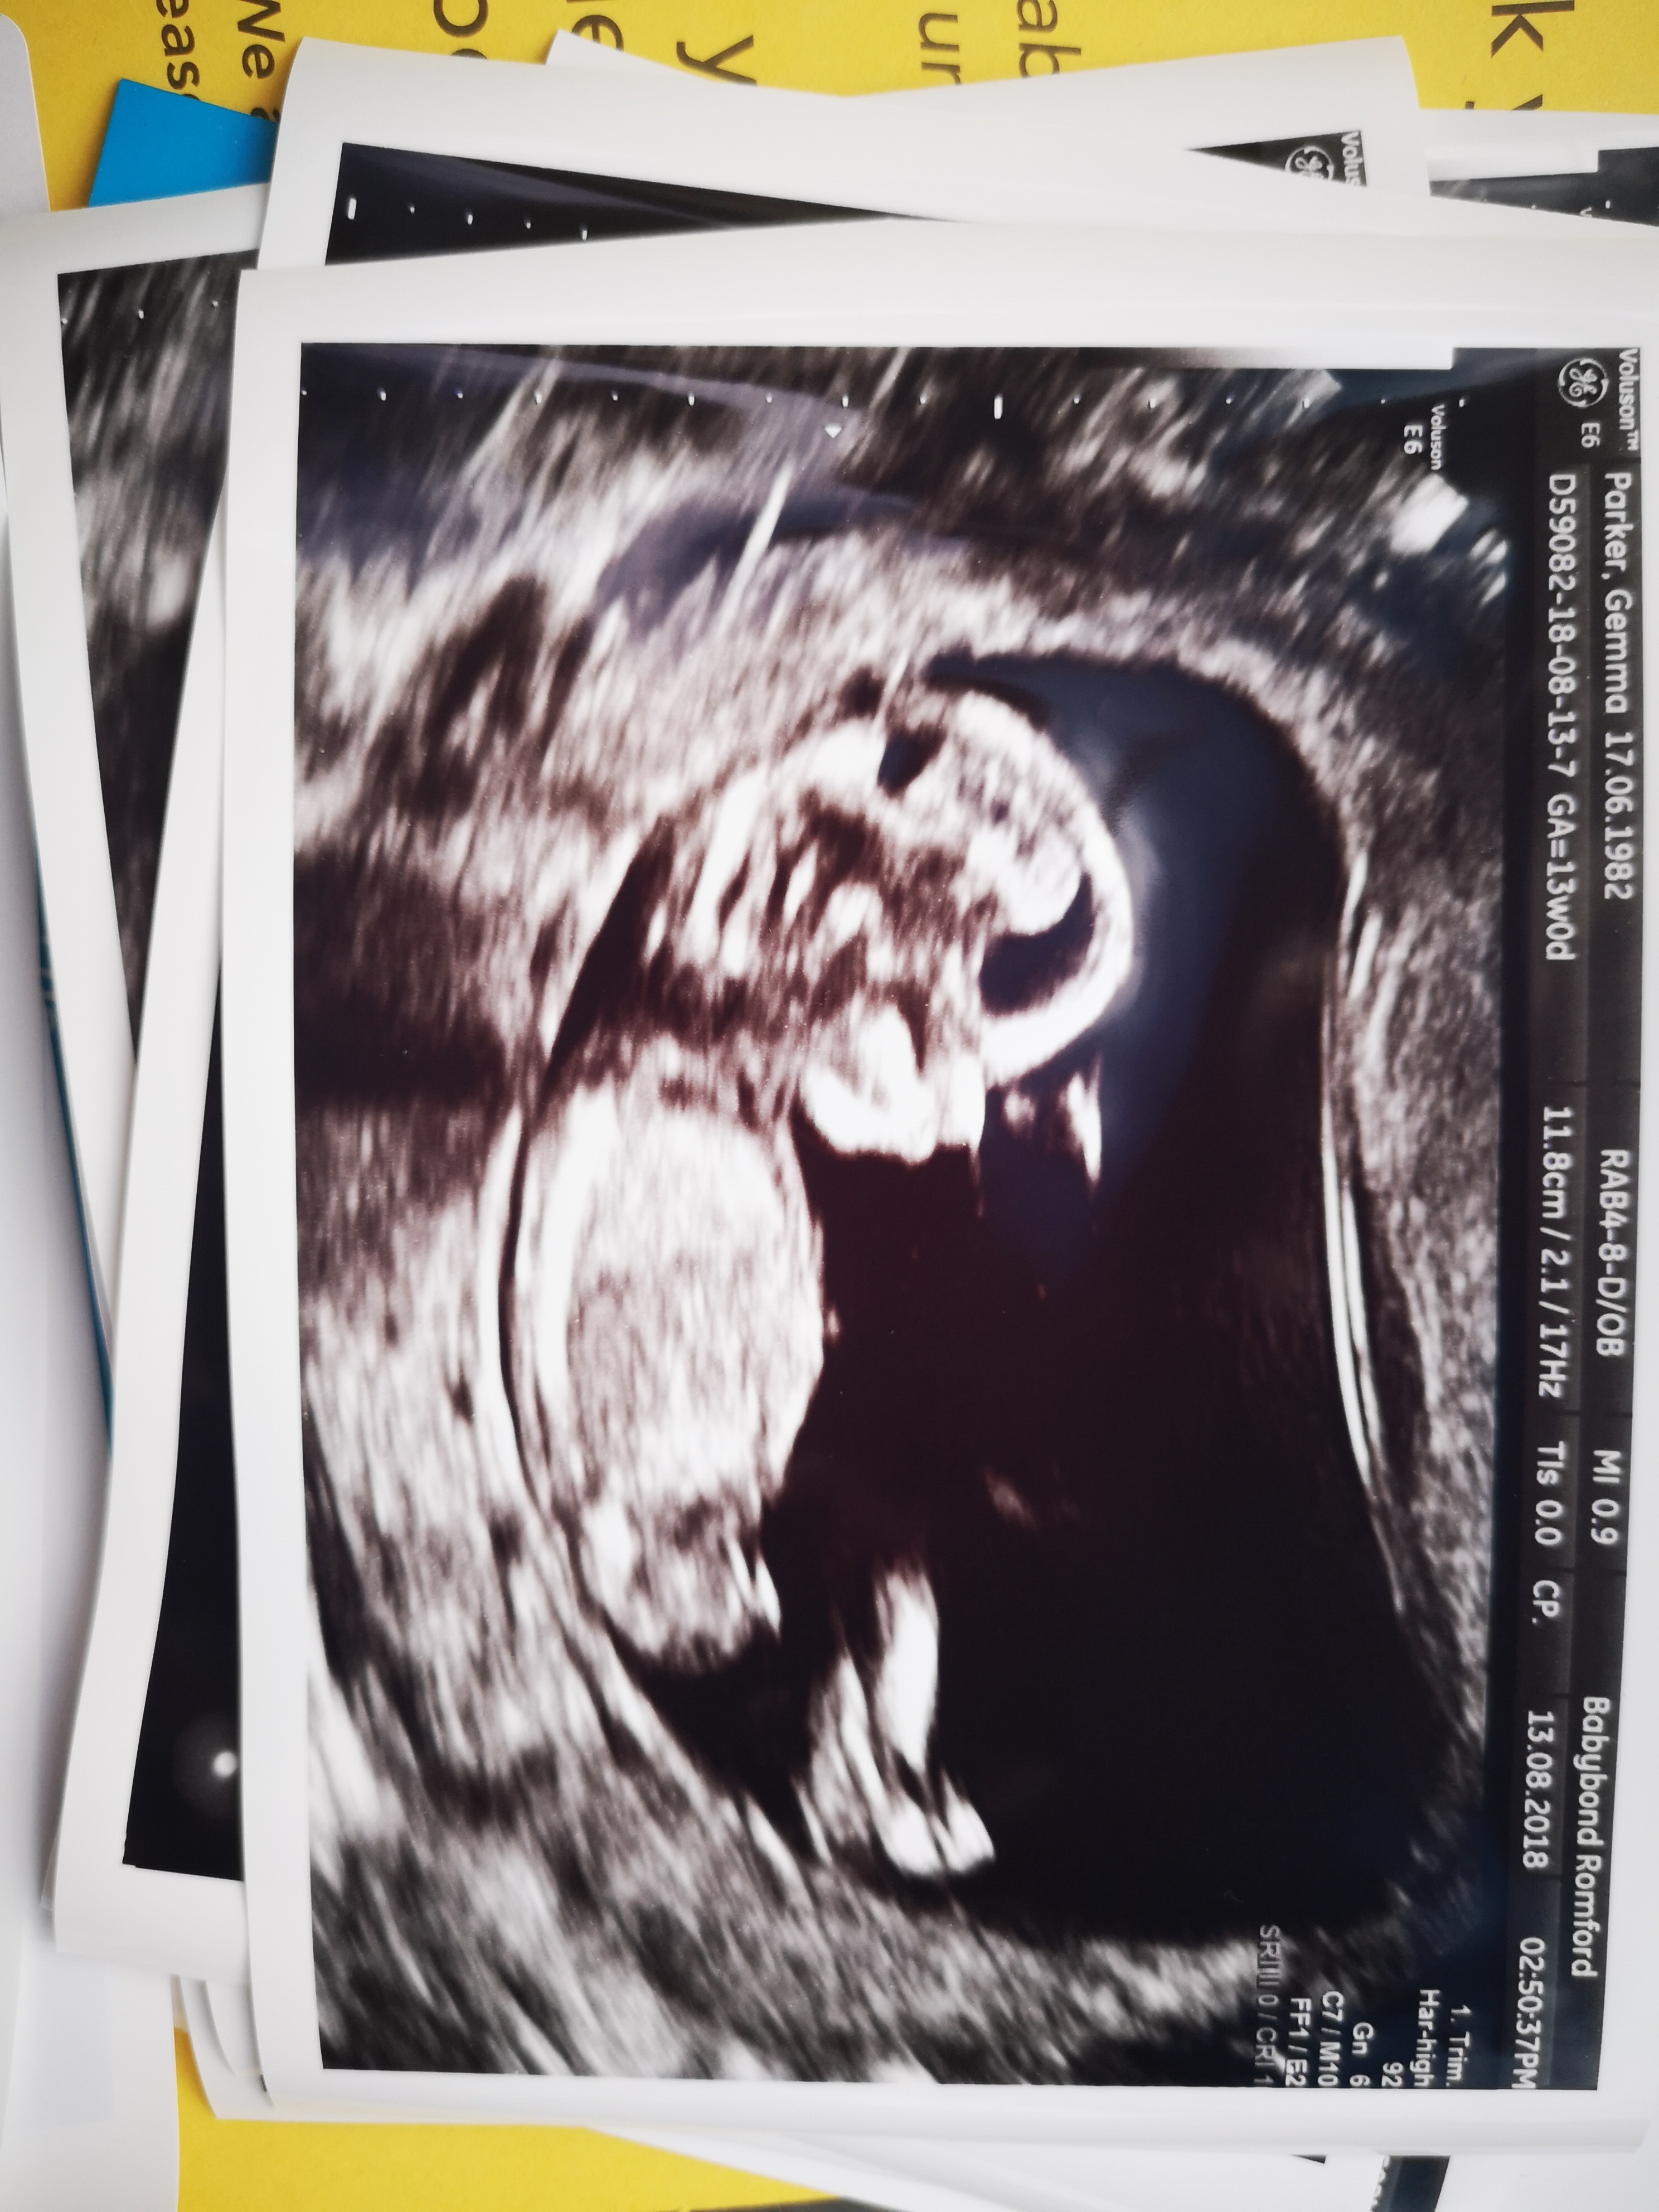

I’m no expert but going to guess boy. Congratulations x

Boy

Boy guess xx

Boy guess from me as well :happy:

Boy guess too

That's definitely a very boy looking nub. :)

Agree. Thinking boy!!!

Boy guess :D